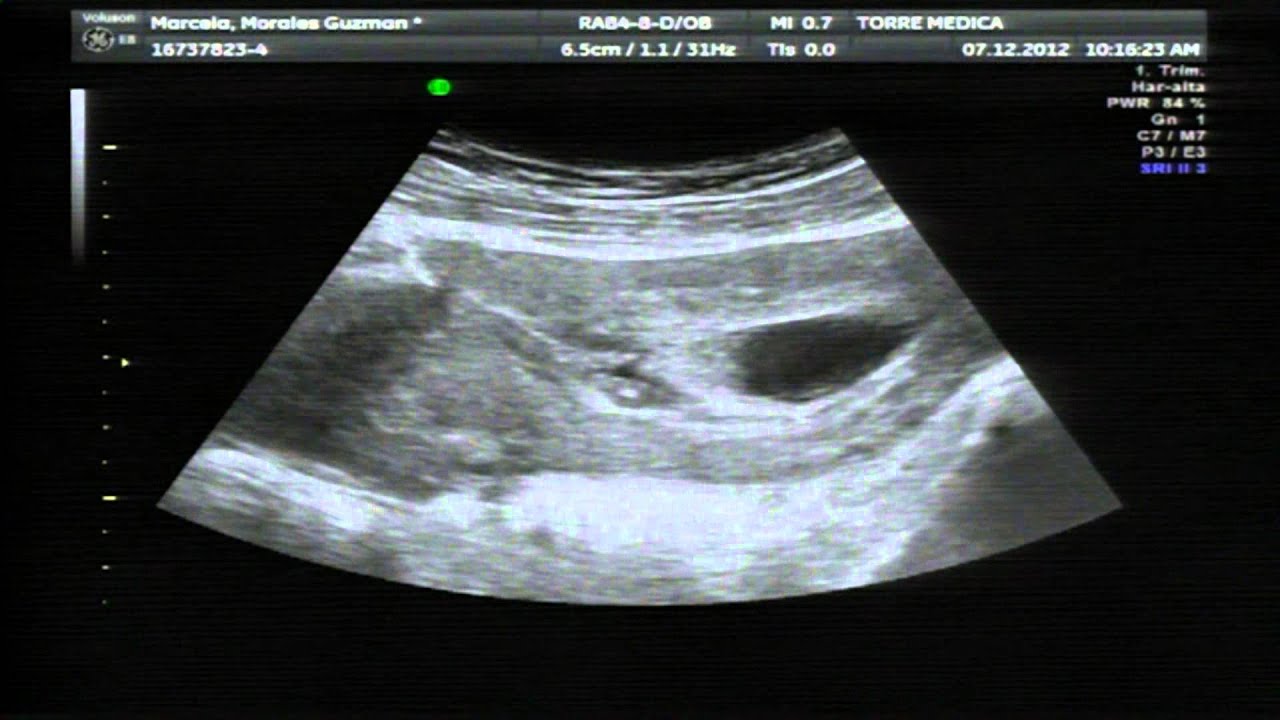

Primera Eco Tras Beta Positiva, De la Beta positiva a la primera ecografía. Unas semanas difíciles de gestionar., 5.91 MB, 04:18, 4,799, C'Est La Vie, Noemí!, 2020-03-12T13:32:38.000000Z, 3, Valores Beta Positiva Fiv Discount Buy, Save 42% | jlcatj.gob.mx, www.jlcatj.gob.mx, 1200 x 1600, jpeg, WebLos primeros días después de una beta positiva suelen ser de felicidad absoluta, pensamos que nuestro sueño se ha cumplido y que, por fin, después de. WebEscorpio, es imposible intuir a través de la beta si se trata de un parto múltiple o no. La mejor manera de saber si se trata de un embarazo múltiple es a través. Web¿Cuándo realizar la primera ecografía de embarazo tras los tratamientos de FIV? Se debe realizar entre la 5ª y la 7ª semana de gestación, es decir entre 3 y 5 semanas tras la., 20, primera-eco-tras-beta-positiva, Novedades y Muebles WebLos primeros días después de una beta positiva suelen ser de felicidad absoluta, pensamos que nuestro sueño se ha cumplido y que, por fin, después de. WebEscorpio, es imposible intuir a través de la beta si se trata de un parto múltiple o no. La mejor manera de saber si se trata de un embarazo múltiple es a través. Web¿Cuándo realizar la primera ecografía de embarazo tras los tratamientos de FIV? Se debe realizar entre la 5ª y la 7ª semana de gestación, es decir entre 3 y 5 semanas tras la.

Web1era eco sin embrión y prueba positiva alguien igual? - Página 3: hoy he tenido mi primera eco en principio estoy de 6.6 pero no habiA embrión ni saco...me he. Web¡Hola de nuevo, preciosas!La #betaespera ha acabado y ya tenemos el resultado... #BetaPositiva :) :) :)¡Os lo cuento todo en el vídeo WebLa beta-hCG se empieza a detectar a partir de la tercera o cuarta semana de embarazo y se incrementa durante todo el primer trimestre. A partir de la semana 12,. Web5º- Semana 7: Todas te harán una eco para confirmar el latido del corazón y la mayoría te darán el alta. (El momento latido no lo vas a olvidar nunca) Como ves sólo hay consenso. WebHola a todas. El día 2 de marzo me hice la transfer del único embri que conseguí en mi primera ICSI. El día 16 me hicieron la beta y dio positivo, así que me. WebLa primera ecografía tras conocer el embarazo es un momento inolvidable y crucial, sobre todo si se produce tras un Tratamiento de Fecundación In Vitro. Aunque los. WebAunque el análisis de la beta hCG en sangre haya dado positivo, normalmente hasta al menos la semana 6 de embarazo no se empieza a ver nada en la. WebHola lunita, claro que lo importante es que la beta esté bien. Y además despues de 7 intentos es mi primer positivo. Solo quiero hacer como un estudio de betas.